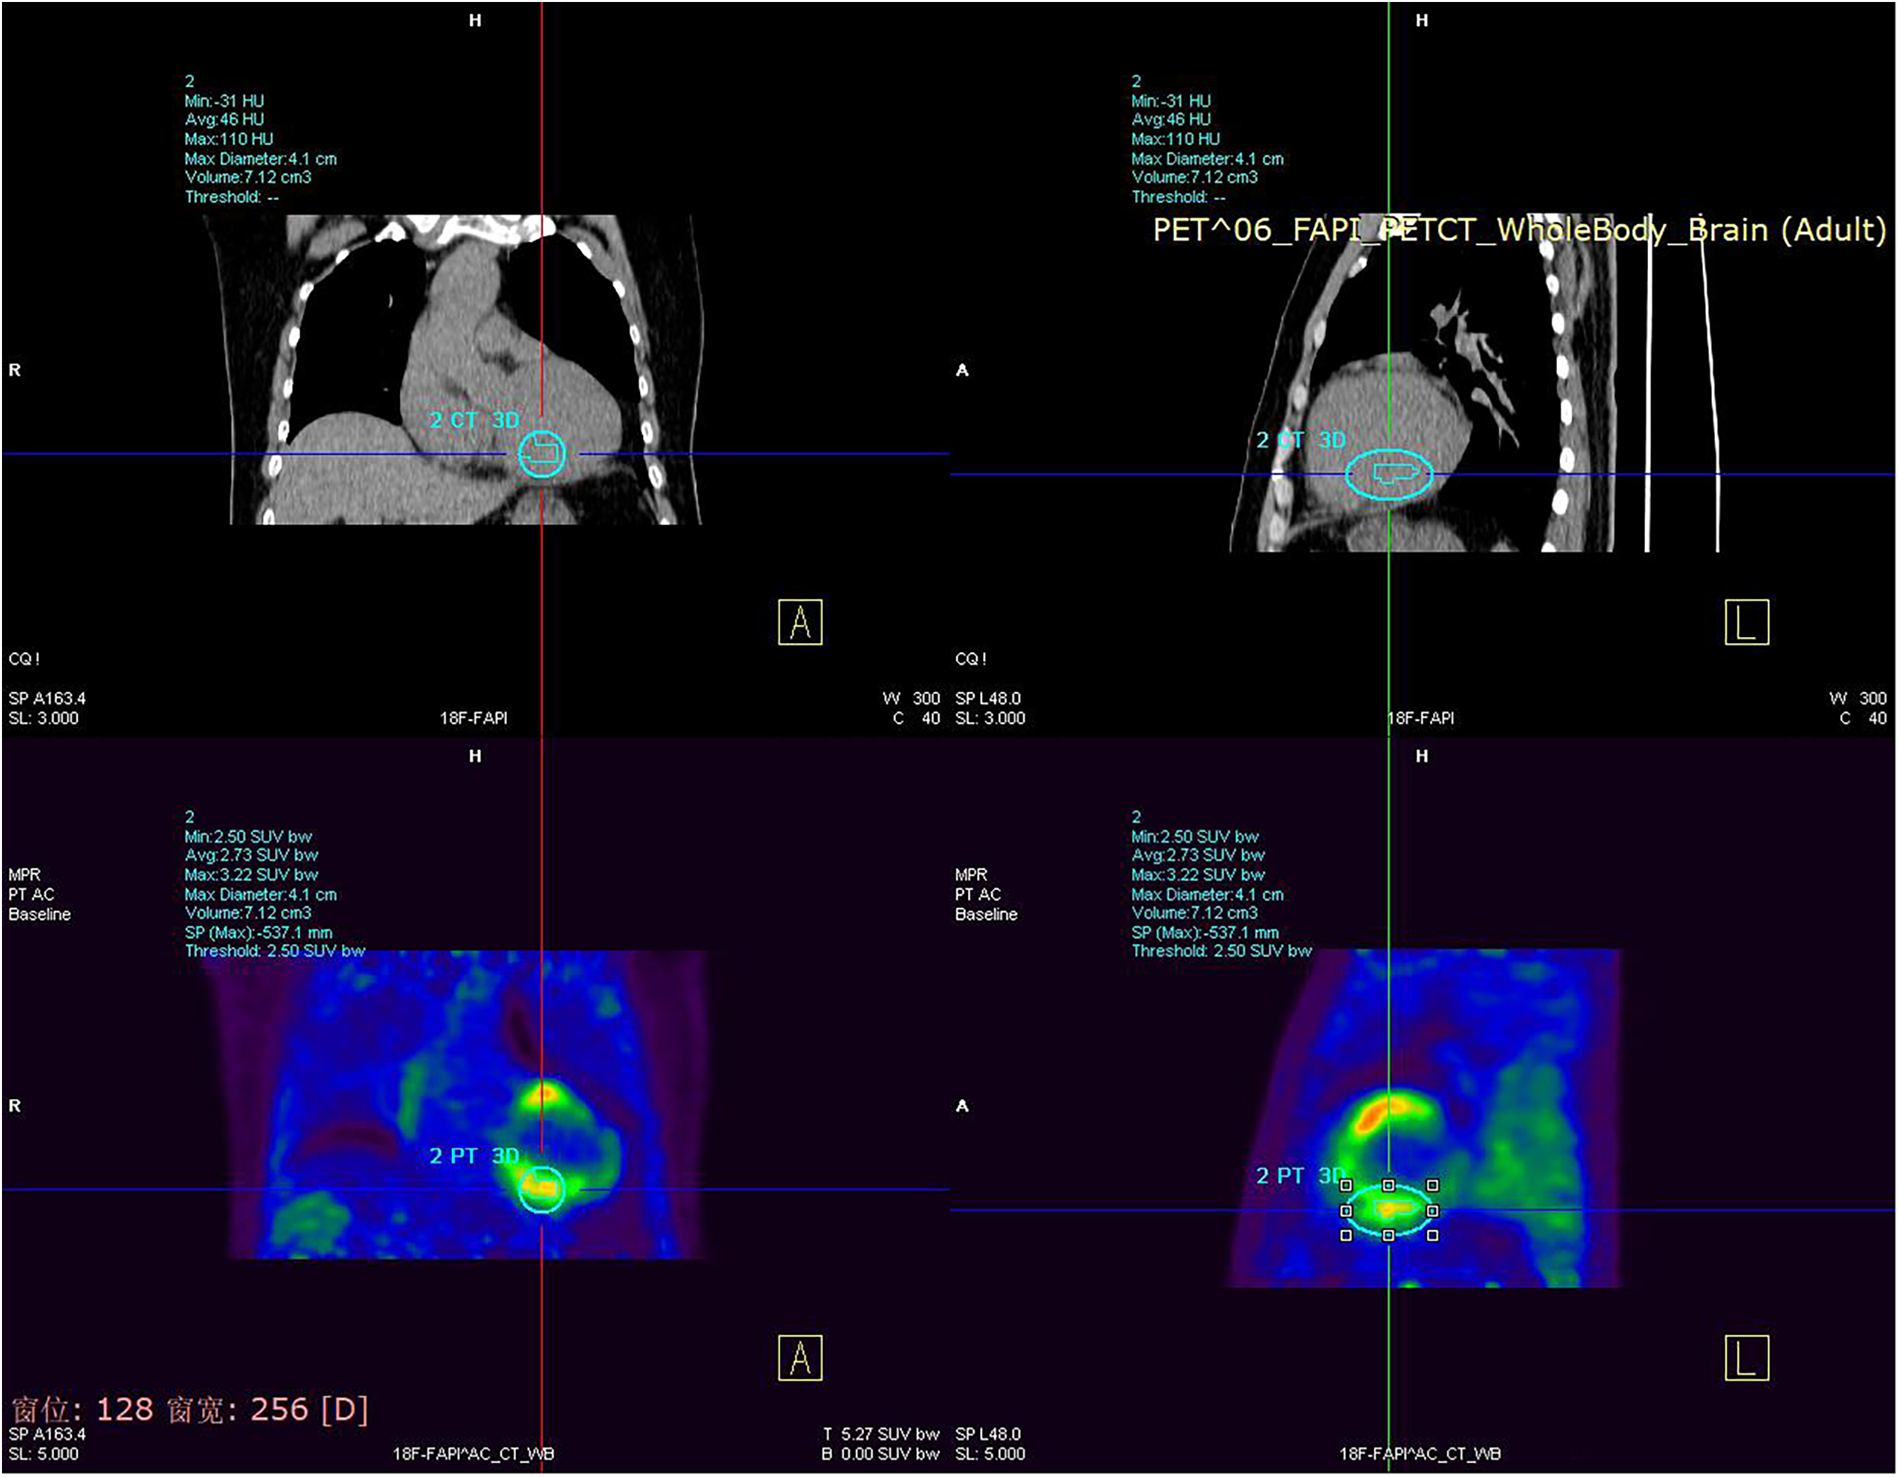

The cardiac ultrasound indicated that the LVEF was 38% and the left atrium and ventricle were enlargement with weakened ventricular septal motion. Moderate mitral and mild aortic and pulmonary regurgitation were also noted. The patient also displayed a troponin sensitivity of 0.023 ug/L. Based on these findings, the local hospital suspected viral myocarditis. The patient was referred to our cardiovascular department for further assessment. The patient's NT pro-BNP level was measured at 1,169 pg/ml, and myocardial nuclide imaging (PET) revealed increased fibroblast activation protein inhibitors(FAPI) uptake throughout the left ventricle and right atrium (Figure 1), supporting a diagnosis of myocarditis. The patient received symptomatic treatment, including hormone anti-inflammatory therapy, nutritional support for myocarditis, and gamma globulin therapy. However, these interventions provided limited relief from wheezing. Coronary angiography showed a left coronary dominant type, with no obvious stenosis in the left main trunk but a 2.7 × 2.3 cm aneurysm in the distal part of the left main trunk. No stenosis was observed in the anterior descending branch, circumflex branch, or right coronary artery (Figure 2). Autoimmune workup, including ANA, anti-dsDNA, ENA antibody profile, and ANCA, returned negative results, ruling out autoimmune causes of the aneurysm. Given the giant aneurysm in the left main trunk, myocarditis, and heart failure with intermediate ejection fraction, open-heart surgery with cardiopulmonary bypass, partial tumor resection, and coronary artery bypass grafting was recommended. However, due to the high risk, the patient and family opted for conservative treatment. As intravascular ultrasound (IVUS) was not performed during coronary angiography, antithrombotic or anticoagulant therapy was not initiated. Instead, the patient was prescribed atorvastatin 20 mg nightly and metoprolol succinate sustained-release 47.5 mg daily.

Figure 1

www.frontiersin.org

Figure 1. Myocardial nuclide imaging (PET) revealed increased FAPI uptake throughout the left ventricle and right atrium.

Coronary aneurysms can have several etiologies, including atherosclerosis, autoimmune diseases, and Kawasaki disease (9, 10). In this case, the patient's autoimmune screening and coronary angiography findings were negative, suggesting a high likelihood of congenital origin. Coronary aneurysms can present with a range of clinical manifestations, such as asymptomatic chest pain, chest tightness, and pericardial tamponade (11). Initially, the patient did not experience any symptoms but was admitted to the hospital this time due to wheezing and dyspnea after catching a cold. Myocardial nuclide imaging was performed to consider myocarditis, but the symptoms did not improve significantly with treatment. Subsequent coronary angiography revealed the presence of a large coronary aneurysm.